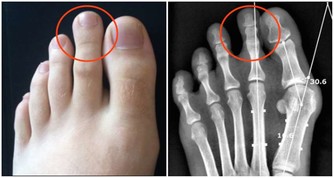

痛風是由單鈉尿酸鹽沉積所致的晶體相關性關節病,與嘌呤代謝紊亂和(或)尿酸排泄減少所致的高尿酸血症直接相關,特指急性特徵性關節炎和慢性痛風石疾病。

主要包括急性發作性關節炎、痛風石形成、痛風石性慢性關節炎、尿酸鹽腎病和尿酸性尿路結石,重者可出現關節殘疾和腎功能不全。

痛風是長期嘌呤代謝障礙,導致體內長期尿酸增高,會在局部形成尿酸結晶,特別是下肢的足背小關節,會導致痛風性關節炎,或是直接形成痛風石,從而會刺激關節面引起反复的疼痛。其臨床特點就是高尿酸血症。但在疼痛急性發作期並不一定的尿酸最高時。